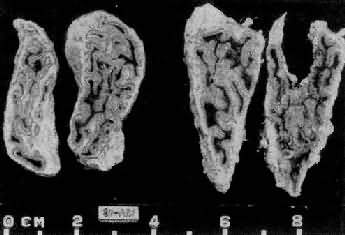

肾上腺皮质弥漫增生(大体)

图15-13 肾上腺皮质弥漫增生(大体)

肾上腺肥大,皮质弥漫性增厚,切面呈脑回状